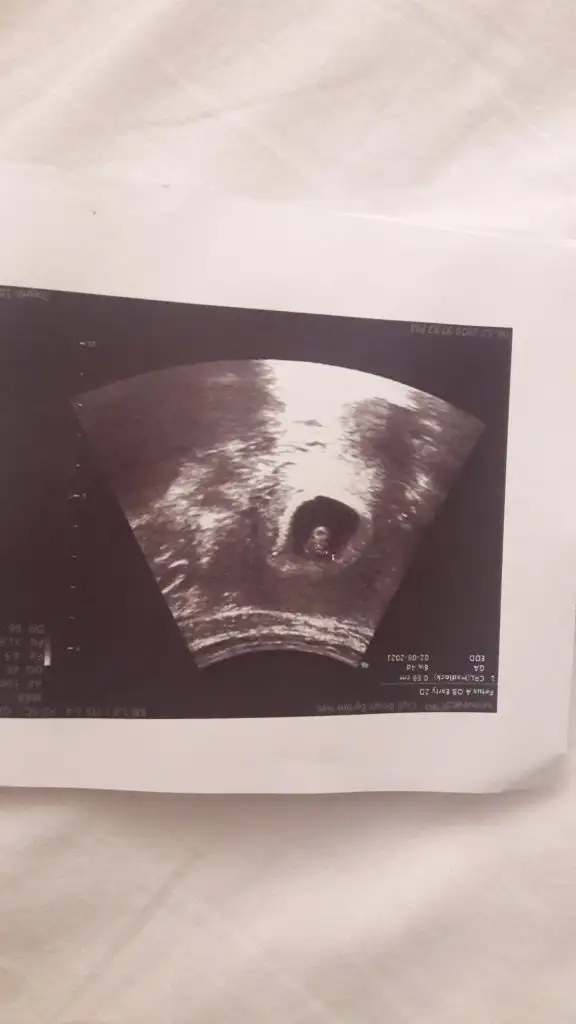

Amin insallah hayırlı bi sekilde canımAmin canım Rabbim sağlıklı hayırlı birer oğluş nasip etsin inşallah bize![]()